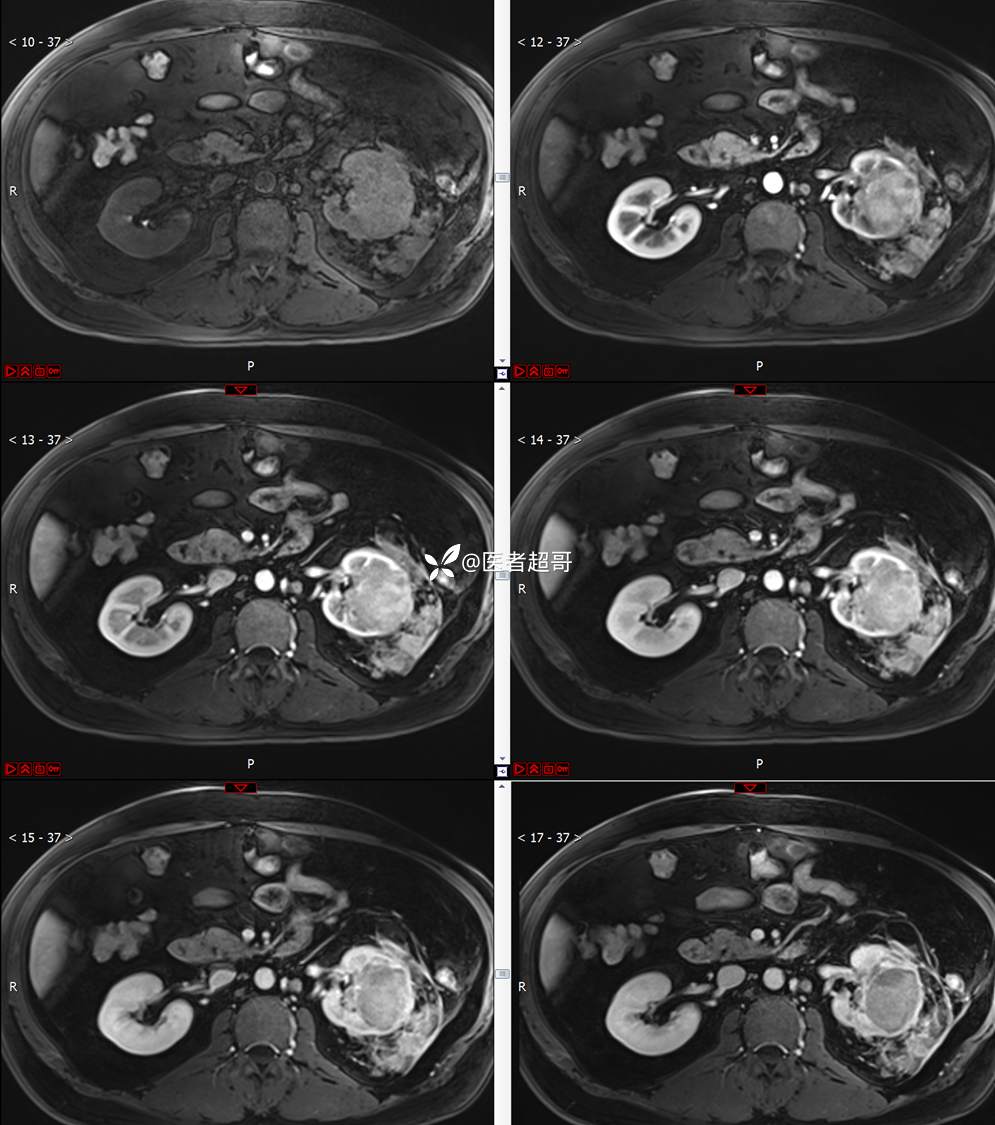

主 诉:查体发现左肾肿物9天。

现病史:患者9天前于附属医院行常规腹部CT检查时,发现左肾占位性病变并肾周脂间隙软组织增多,自述无明显腰腹部不适,无尿频、尿急、尿痛及肉眼血尿,未予特殊治疗,患者近期无头晕头迷,胸闷气急,腹胀腹泻及其他部位明显不适,遂至我院就诊,门诊以“肾肿物”收入院,患者自发病以来,精神可,睡眠饮食可,大便正常,体重无明显减轻。